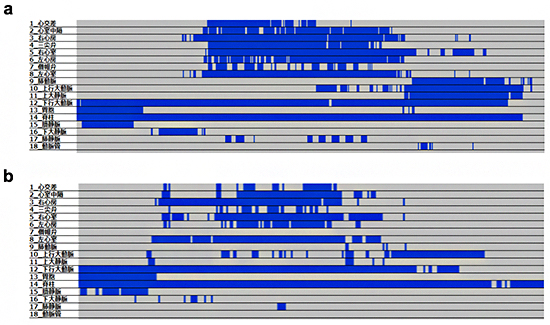

さらに、各部位について確信度の累積・時間経過をレポートし、各部位の確信度を一覧表示する検査結果表示システムも開発しました(図3、特許出願中)。超音波検査において走査断面動画の確認には、静止画とは異なり再生時間を要するため、一覧性が悪いことが問題となっていました。

しかし、本手法を用いることで、一度に動画全体における各部位の検知具合を確認することが可能になり、確認に必要な時間を大幅に削減できました。また、物体検知技術を用いて各部位を検知しているため、検査者間の技術格差によらず検査結果が一定になります。さらに、どの部位が異常判定に影響したのかを一覧表示で把握・説明できるため、考えうる先天性心疾患を推定でき、検査者が超音波専門医や小児循環器内科医、小児心臓血管外科医に相談する際にも有用となります。

図3 検査結果一覧表示システム

診断に必要な胎児心臓と周辺臓器の18部位について、確信度の累積・時間経過をレポートし、各部位の確信度を一覧表示する(横軸:時間経過、青色:一定以上の確信度で検知されている。灰色:検知されていない)。動画情報を2次元データで一覧表示し、正常胎児のデータ(a)と比較することで、より簡便にどの部位が異常判定に影響したのかを把握して説明することが可能となる(b.ファロー四徴症)。